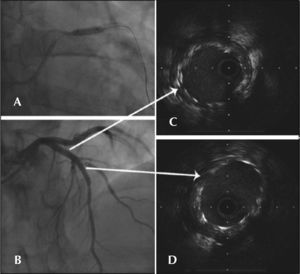

After performing the kissing balloon technique with a Sequent 3 × 20mm balloon that was inflated to 12atm in the left anterior descending artery, and a Sequent 3 × 20mm balloon that was inflated to 10atm and directed to the diagonal branch (Fig. 1 D), dilatation of the proximal third of the stent was performed with a Quantum 4 × 12mm balloon at 12atm. The guidewire in the diagonal branch was retreated and the final angiographic control was performed. However, an equivocal image (haziness) was observed in the proximal stent border, thus IVUS was performed (Figure 2). IVUS demonstrated strut deformity in the proximal stent border with the IVUS catheter positioned outside the stent lumen. The guidewire was also outside the stent lumen in its proximal border (Figure 3 A and B). This guidewire was left in the same position, and another guidewire was advanced through the crushed struts followed by a new IVUS evaluation, which confirmed its correct position (Figures 3 C and D).

– In A, angiography demonstrating the guidewire behind the proximal stent struts (arrow). In B, IVUS demonstrating the catheteoutside the stent lumen. In C, angiography immediately after passag of a new guidewire inside the crushed struts (arrow). In D, IVUS demonstrating the correct guidewire position.